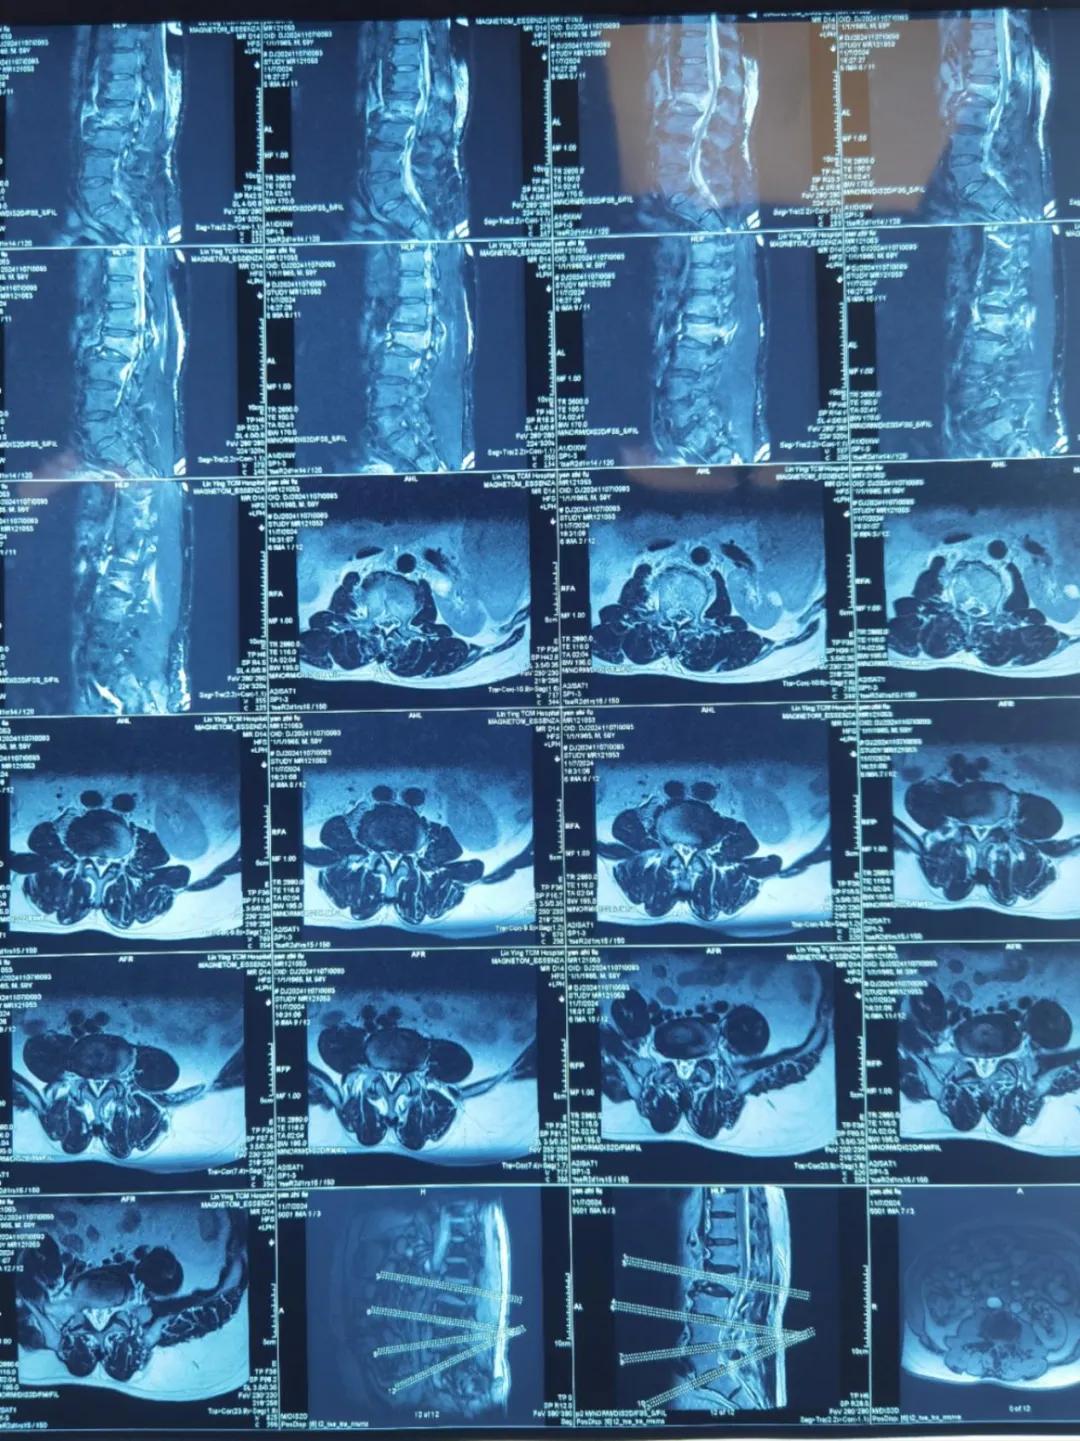

“醫生,這是之前的檢查結果,還需要再做檢查嗎?”閆大叔從外院轉來被推進智能微創骨科。幾天前,他在老家的中醫院進行了抽血檢驗和磁共振檢查,因為腰疼嚴重、行動不便檢查過程也十分不易。

智能微創骨科副主任李鵬認真檢查了閆大叔帶來的片子,還有電腦系統上彈出來的檢驗結果。外院的核磁和X線可以清楚的看到情況已經比較嚴重,需要盡快手術。沒有二次檢查,不僅節省患者就醫費用,還使就醫更高效、便捷直接入院接受治療。閆大叔懸著的心放了下來,其他醫院的片子能直接用,檢查在家附近的醫院做,手術在漯河市骨科醫院做,便捷的結果'互認'讓他直夸“真方便!咱老百姓更省心、更放心了!”